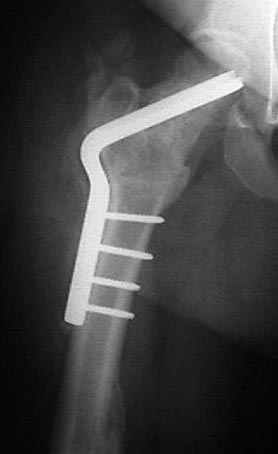

5:24 Рентгенограмма таза, вызывают врача ортопеда (снимок N1), его диагноз: закрытый переломо-вывих правого тазабедренного сустава, получает добро на закрытую репозицию в приемном отделении

N 2

7:30 начало операции, больной на спине, попытка репозиции после анестезии N3, укладка больного на боку, доступ Kocher- Langenbeck, состояние седалищнего нерва около 2.5см кровоподтек, через joistick головка бедра приподнята, освобовождение сустава, фрагмент заднего края более 3х4 см репонирован на свое место. После промывания

сустава, репозиция вывиха (N4), фиксация фрагмента 2.7(4) мм шурупами и допольнительно реконструктивной пластиной на 8 дырок, фиксация 3.5мм шурупами проксимально и дистально.

Интраоперционные N5 косая запирательная и N6 подвздошный снимок

11:50 больной в послеоперационной, рентгенограмма N7, компьютерная томограмма в тот же день N8-10